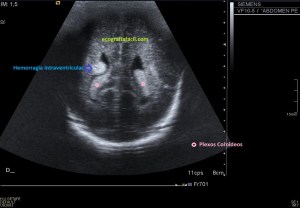

Con la eco pasa igual…cuando queremos estudiar, por ejemplo, el recto anterior del muslo en axial,perfecto…pero en longitudinal, como la imagen 2, se complica porque desde la rótula a la inserción en la cadera, tenemos mucho recorrido. En este caso hacemos lo mismo que cuando hacemos la foto del atardecer…nos ponemos en un extremo, activamos la funciona, recorremos suave y continuamente por la anatomía que queremos fotografiar y ya está…mira la pantalla y no el movimiento de tu mano,como si hicieses la foto, ves la pantalla,pero no como mueves el teléfono.

Es muy útil para lesiones que han crecido mucho y no podemos conjugar en una sola imagen, por ejemplo, un lipoma, cuando superan la medida de la huella de la sonda no son medibles, hay que usar «panoramic view», y como este caso, otros muchos.